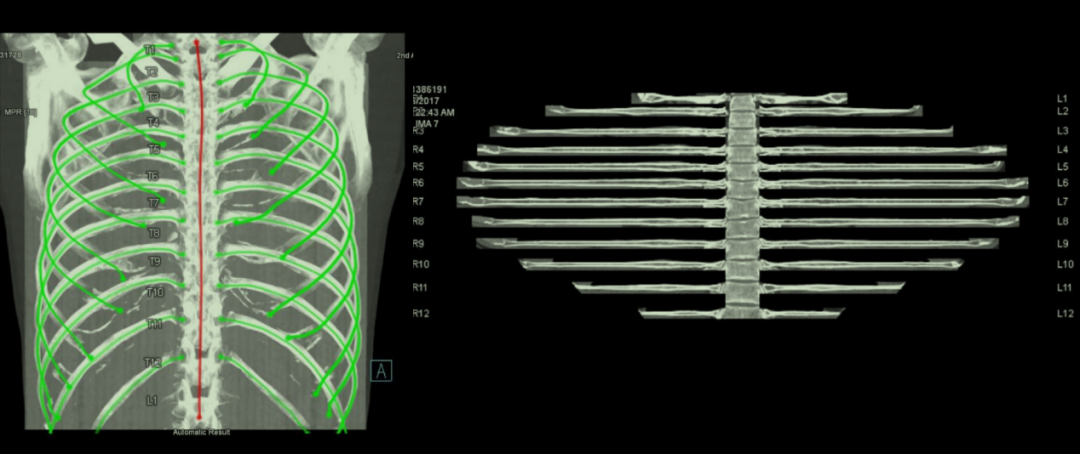

肋骨曲面重建